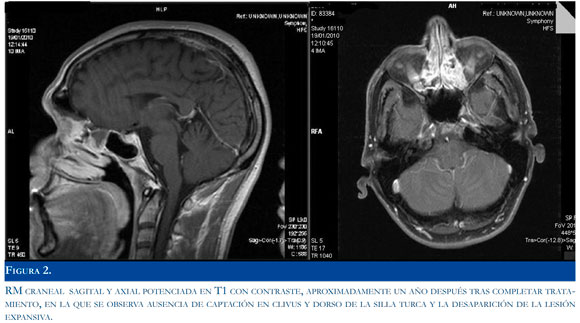

Los cultivos para anaerobios, aerobios y hongos del material pulmonar fueron negativos. Se obtuvo positividad en el cultivo para Mycobacterium Tuberucu-losis unos 20 días después de la toma de la muestra pulmonar. El diagnóstico final fue osteomielitis tuberculosa de clivus asociada a infección pulmonar con meningitis por descubrirse el crecimiento de Mycobacterium Tuberculosis en el cultivo del material extraido de uno de los abscesos pulmonares se cambió a tratamiento antituberculoso oral polifar-macológico considerado de primera línea (isoniazida, rifampicina, pirazinamida) durante 18 meses. Aproximadamente al cabo de los tres primeros meses desapareció totalmente la paresia del VI par derecho. Los controles de RM craneal también mostraron progresiva mejoría (Figura 2).

La osteomielitis tuberculosa de clivus (en este caso con afectación de tejidos vecinos), es una localización descrita en la literatura en escasas publicaciones y más propia de áreas con alta incidencia y prevalencia de tuberculosis (1,4). En este caso se inició con clínica neurológica y LCR poco específicos (cefalea sin otros síntomas durante semanas y leve pleocitosis linfocítica) asociada a nodulos pulmonares. Aunque los hallazgos de la RM craneal con cambio de señal y captación de contraste en el clivus (Figura 1) plantearan el diagnóstico diferencial tanto de causas inflamatorias como neoplásicas, la aparición de nódulos pulmonares abscedados hicieron que se sospechara causa infecciosa por lo que se procedió a instaurar tratamiento de amplio espectro intravenoso con linezolid y meropenem. La negatividad de las tinciones microbiológicas del LCR y del material pulmonar, de la reacción de la cadena de la polimerasa para micobacterias en LCR y del resto de pruebas microbiológicas y serológicas (excepto la serología de Borrelia sp en sangre a títulos bajos con serología negativa en LCR), hizo depender el diagnóstico de los cultivos del material extraído de los nódulos pulmonares. La leve a moderada pleocitosis y el aumento de presión en LCR sin otros cambios y la negatividad microbiológica, se explica por la existencia de una meningitis por vecindad.